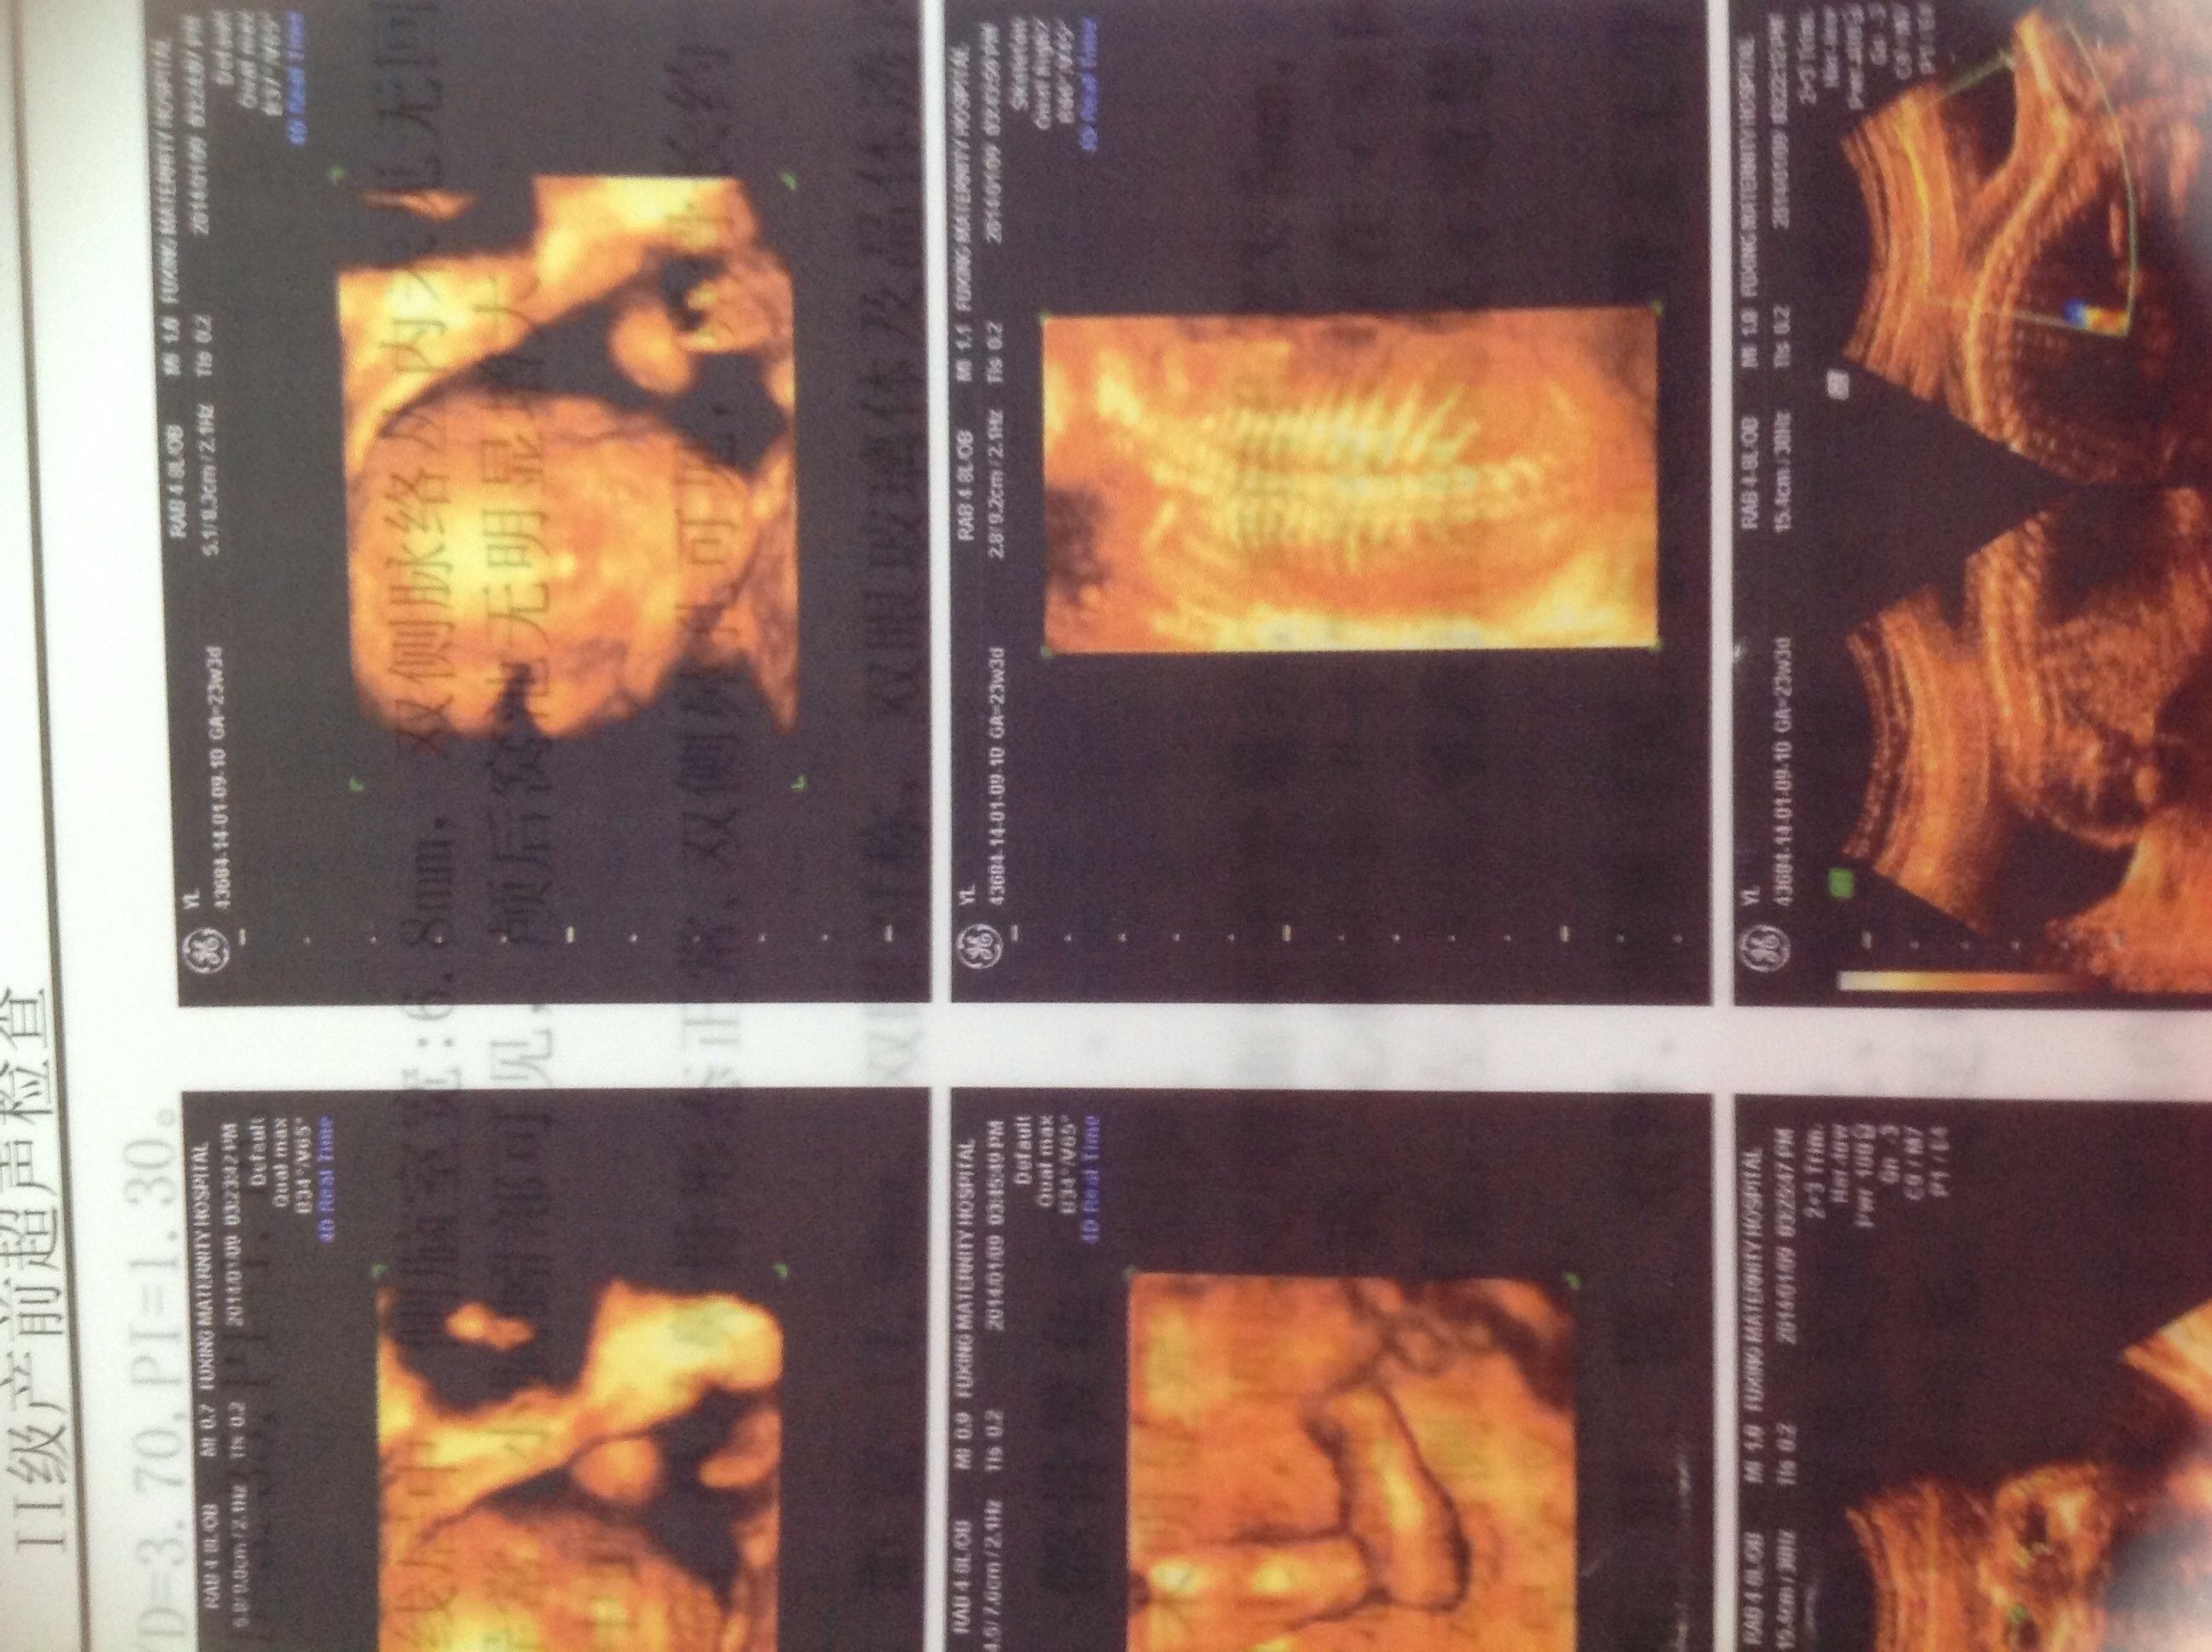

这是前两天给宝宝拍的四维彩超,现在已经22周啦,麻烦各位告诉我下是男宝宝还是女宝宝我好早做准备呢 万分感谢 点击展开 匿名用户 2014-01-16 21:11 为您推荐: 其他回答 病情分析: 根据您上述描述的情况我考虑一般看男孩还是女孩这是违法的,并且看男孩还是女孩这样也是看不出来的。 指导意见: 我考虑您就不要有这种想法了,我考虑您最好就顺其自然吧,这样没有什么需要特殊准备的。 匿名用户 2014-01-17 16:02 相关问题 在广州去哪里照四维彩超好点!?谢谢大家,麻烦知道的宝妈们告诉我一下 潞河医院做一个四维彩超多少钱啊,有知道的吗,麻烦告诉我一下 武汉哪里可以照四维彩超啊?需要花多少钱?麻烦有经验的告诉我!谢谢